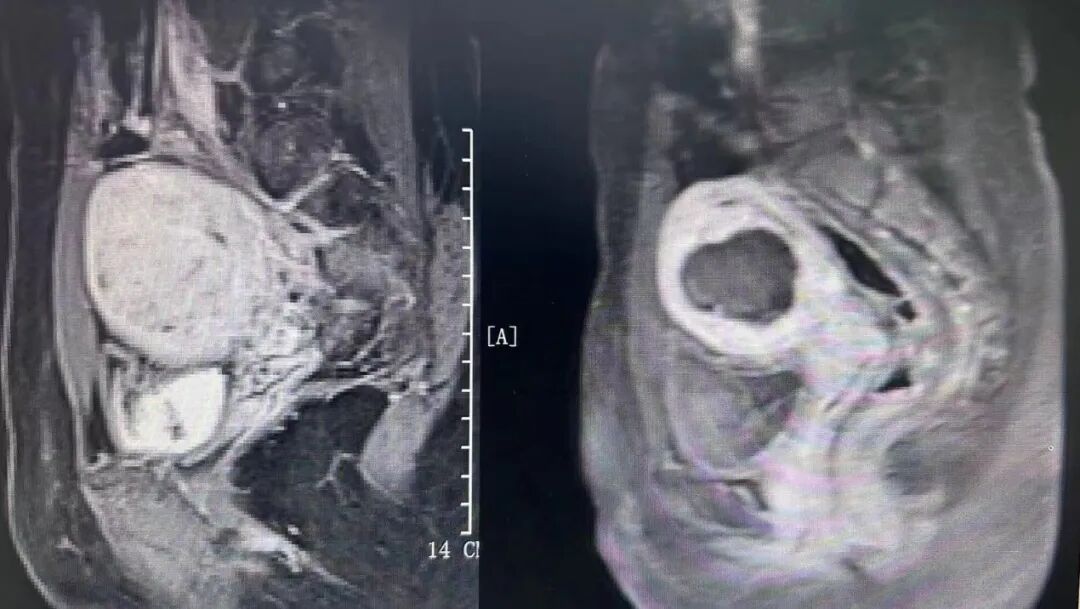

手術(shù)在鎮(zhèn)靜鎮(zhèn)痛下進(jìn)行,分別歷時35分鐘、68分鐘順利完成兩臺手術(shù)。與傳統(tǒng)的開腹手術(shù)、腔鏡手術(shù)相比,聚焦超聲消融手術(shù)具有無創(chuàng)傷、并發(fā)癥少、預(yù)后快等優(yōu)點,對身體子宮傷害小,術(shù)后恢復(fù)快。兩位子宮肌瘤患者對治療非常滿意,對醫(yī)生的精湛醫(yī)術(shù)表示衷心感謝,術(shù)后第二天均順利出院。

本技術(shù)已用于子宮肌瘤、子宮腺肌病、胎盤植入、瘢痕妊娠、腹壁子宮內(nèi)膜異位癥、宮頸炎、宮頸HPV感染、外陰白斑等多種疾病的治療,截至目前已成功治療接近2000例患者,取得了滿意的治療效果。